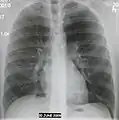

Normal AP CXR

Normal AP CXR Normal lateral CXR